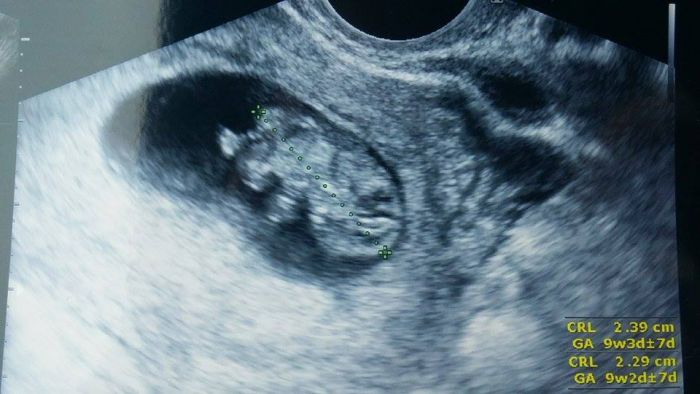

holky, dnes jsem byla na kontrole. Dostala jsem občanku na miminko a byla to fakt nádhera, protože tam sebou pořád mrskal a mával ručičkama. Fotka nádherná. Prý je to pořádný cvalík :-D jinak měříme skoro 2,5cm a odpovídáme 9+3 a rosteme prý podle tabulek. Takže jsem hrozně šťastná a spokojená.

Moc gratuluji Alice, krásná fotka, je zajímavé když jsem se ptala jestli i podle tabulek odpovídáme tak prý jo a dle uz 9+3 máme 2,91cm :-) a ty vlastně přesně víš kdy jsi otehotnela, že? Já právě ne :-) ale asi budeme podobně